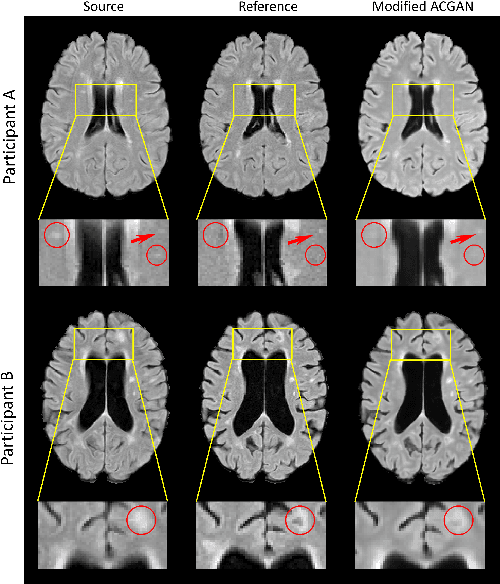

Abstract:Multiple Sclerosis (MS) is a chronic progressive neurological disease characterized by the development of lesions in the white matter of the brain. T2-fluid-attenuated inversion recovery (FLAIR) brain magnetic resonance imaging (MRI) provides superior visualization and characterization of MS lesions, relative to other MRI modalities. Longitudinal brain FLAIR MRI in MS, involving repetitively imaging a patient over time, provides helpful information for clinicians towards monitoring disease progression. Predicting future whole brain MRI examinations with variable time lag has only been attempted in limited applications, such as healthy aging and structural degeneration in Alzheimer's Disease. In this article, we present novel modifications to deep learning architectures for MS FLAIR image synthesis, in order to support prediction of longitudinal images in a flexible continuous way. This is achieved with learned transposed convolutions, which support modelling time as a spatially distributed array with variable temporal properties at different spatial locations. Thus, this approach can theoretically model spatially-specific time-dependent brain development, supporting the modelling of more rapid growth at appropriate physical locations, such as the site of an MS brain lesion. This approach also supports the clinician user to define how far into the future a predicted examination should target. Accurate prediction of future rounds of imaging can inform clinicians of potentially poor patient outcomes, which may be able to contribute to earlier treatment and better prognoses. Four distinct deep learning architectures have been developed. The ISBI2015 longitudinal MS dataset was used to validate and compare our proposed approaches. Results demonstrate that a modified ACGAN achieves the best performance and reduces variability in model accuracy.

Abstract:Multiple Sclerosis (MS) is a chronic neurological condition characterized by the development of lesions in the white matter of the brain. T2-fluid attenuated inversion recovery (FLAIR) brain magnetic resonance imaging (MRI) provides superior visualization and characterization of MS lesions, relative to other MRI modalities. Follow-up brain FLAIR MRI in MS provides helpful information for clinicians towards monitoring disease progression. In this study, we propose a novel modification to generative adversarial networks (GANs) to predict future lesion-specific FLAIR MRI for MS at fixed time intervals. We use supervised guided attention and dilated convolutions in the discriminator, which supports making an informed prediction of whether the generated images are real or not based on attention to the lesion area, which in turn has potential to help improve the generator to predict the lesion area of future examinations more accurately. We compared our method to several baselines and one state-of-art CF-SAGAN model [1]. In conclusion, our results indicate that the proposed method achieves higher accuracy and reduces the standard deviation of the prediction errors in the lesion area compared with other models with similar overall performance.